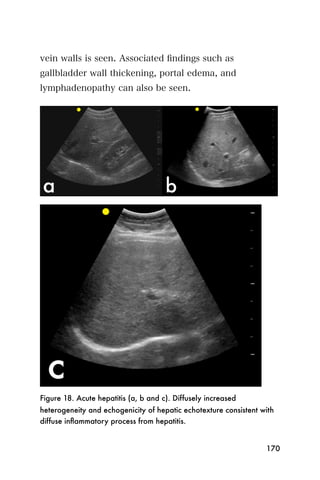

112

While all machines are different, here is an example of